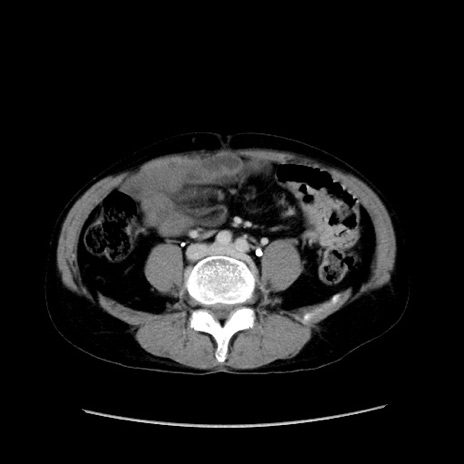

症例37(横断像)

【症例】40歳代 男性

【主訴】腹痛

【現病歴】4時間ほど前に電車に乗車中に臍部上より腹痛出現。徐々に増悪し起立困難となり、救急外来受診。生ものは数日食べていない。今朝お雑煮を食べた。

【身体所見】BT 36.8℃、BP 117/84mmHg、HR 91/min、SpO2 97%、苦悶様、腹部:臍上部広範囲圧痛あり、反跳痛±

【データ】WBC 8100、CRP 0.03